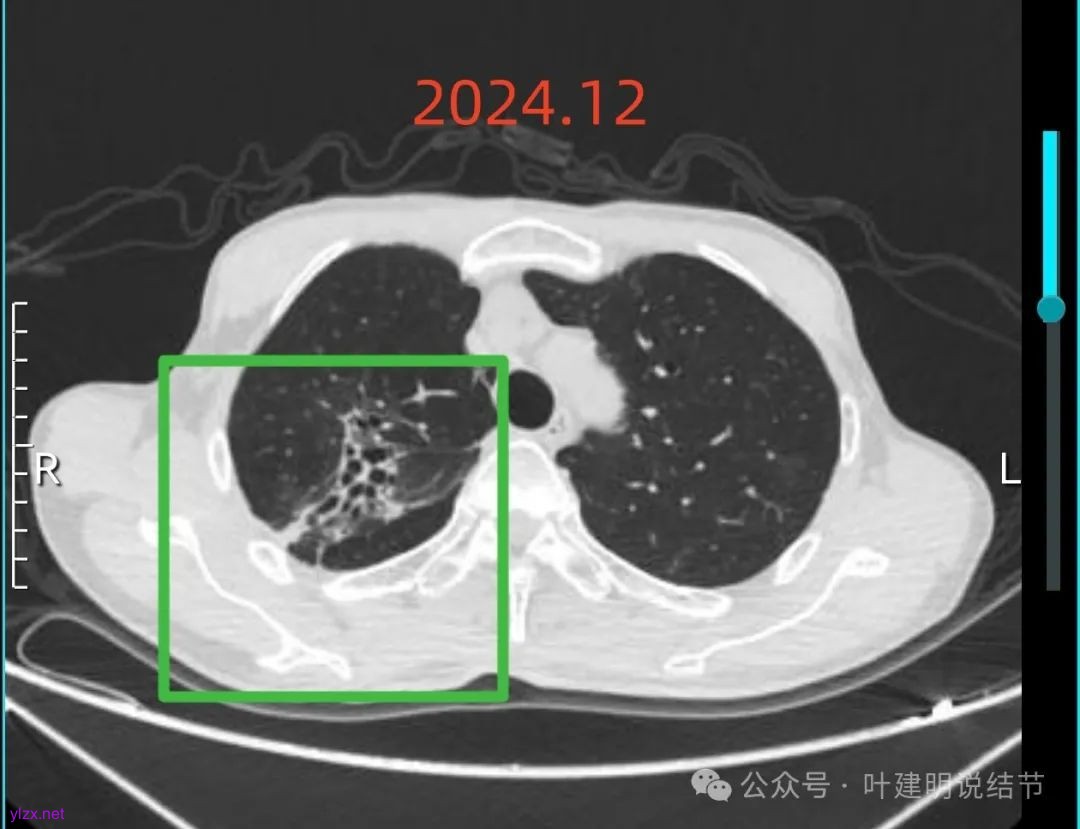

再来看2024年12月时的影像:

右上混合阴影也没有明显进展,则同样要更倾向确实是支气管扩张伴慢性炎与纤维增生的关系,可随访。